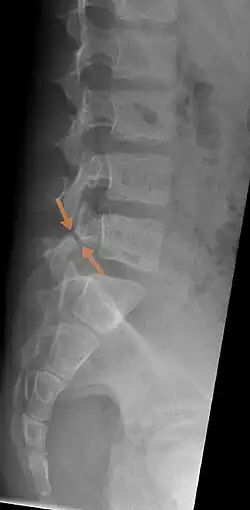

Arrows show break in pars interarticularis at L5. X-Ray of lumbar spine, lateral projection, in an 11-year-old boy